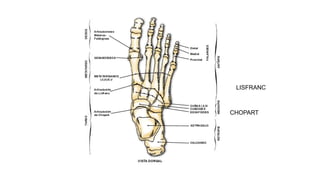

HUESOS DEL TARSO

LISFRANC

CHOPART